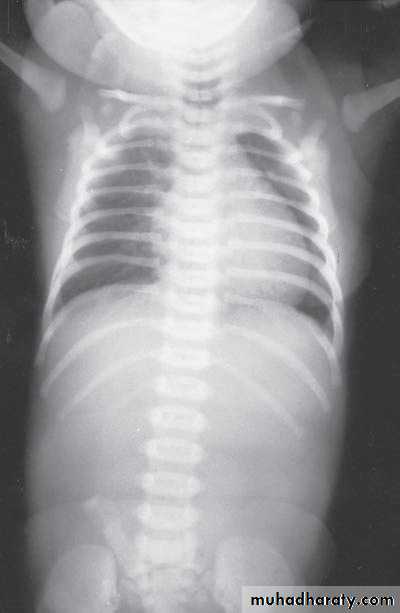

Respiratory Distress in the NewbornFirst photo:

Diagnosis: eventration of diaphragmDescription: mild dextrocardia – recurrent chest infection – diaphragm is present

mild distress - 7 months age baby – less number of intestinal loops in the chest

there is lung tissue in the chest - Paradoxical movement of the diaphragm.

Treatment: plication of the hemi-diaphragm (through thoracic approach).